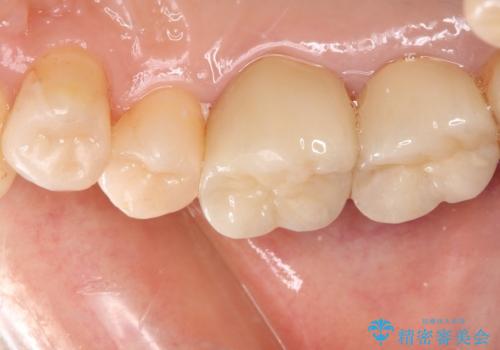

- 奥歯の銀歯をセラミックの白い歯にして、しみる症状も改善したいとのことで来院された患者様です。

知覚過敏の症状が強い歯と、銀歯の範囲や銀歯の下のむし歯が大きい歯は、インレー修復では対応が難しいためオールセラミッククラウンで、インレー修復で対応が可能な歯ではセラミックインレーにて修復することとしました。

知覚過敏の症状はなくなり、希望通りの白い歯になったと、患者様は大変満足されました。